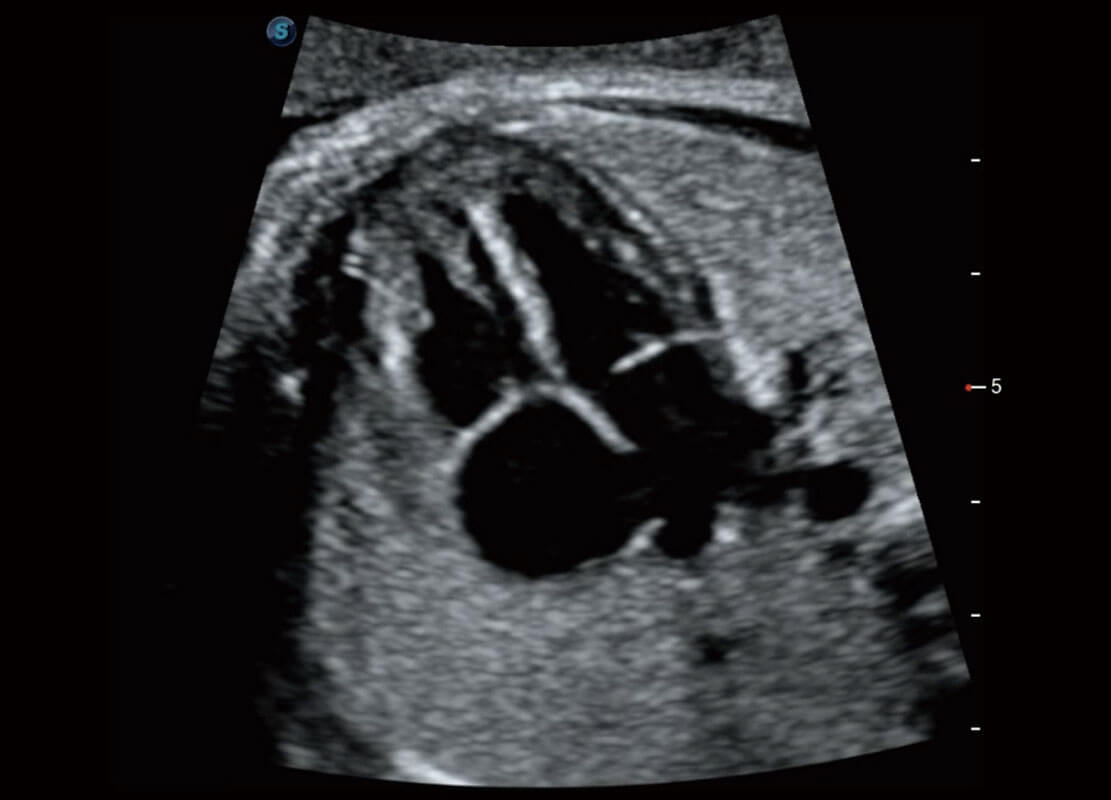

四腔切面

四腔心血流

右室双出口

胎心容积成像